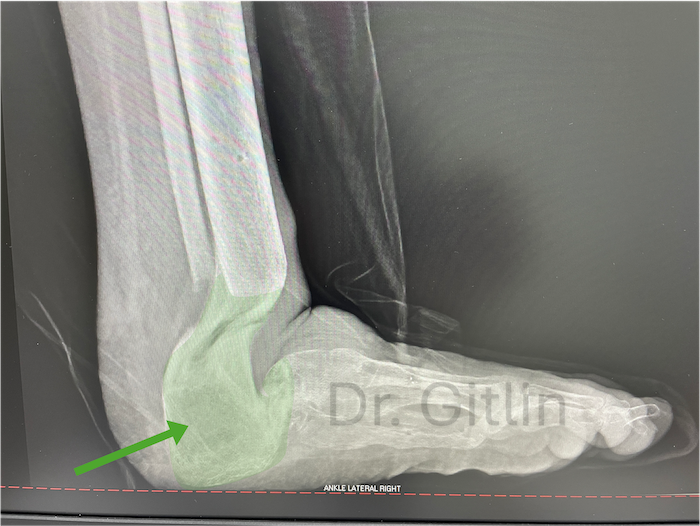

The picture below shows in the green color all of the new bone we created. Even though it will never look like the actual bones and joints it still functions to give the patient a usable limb. Under this X-ray you can see a picture of the patients foot after surgery. The patient is now over two years after surgery and can normally walk and run with his children.